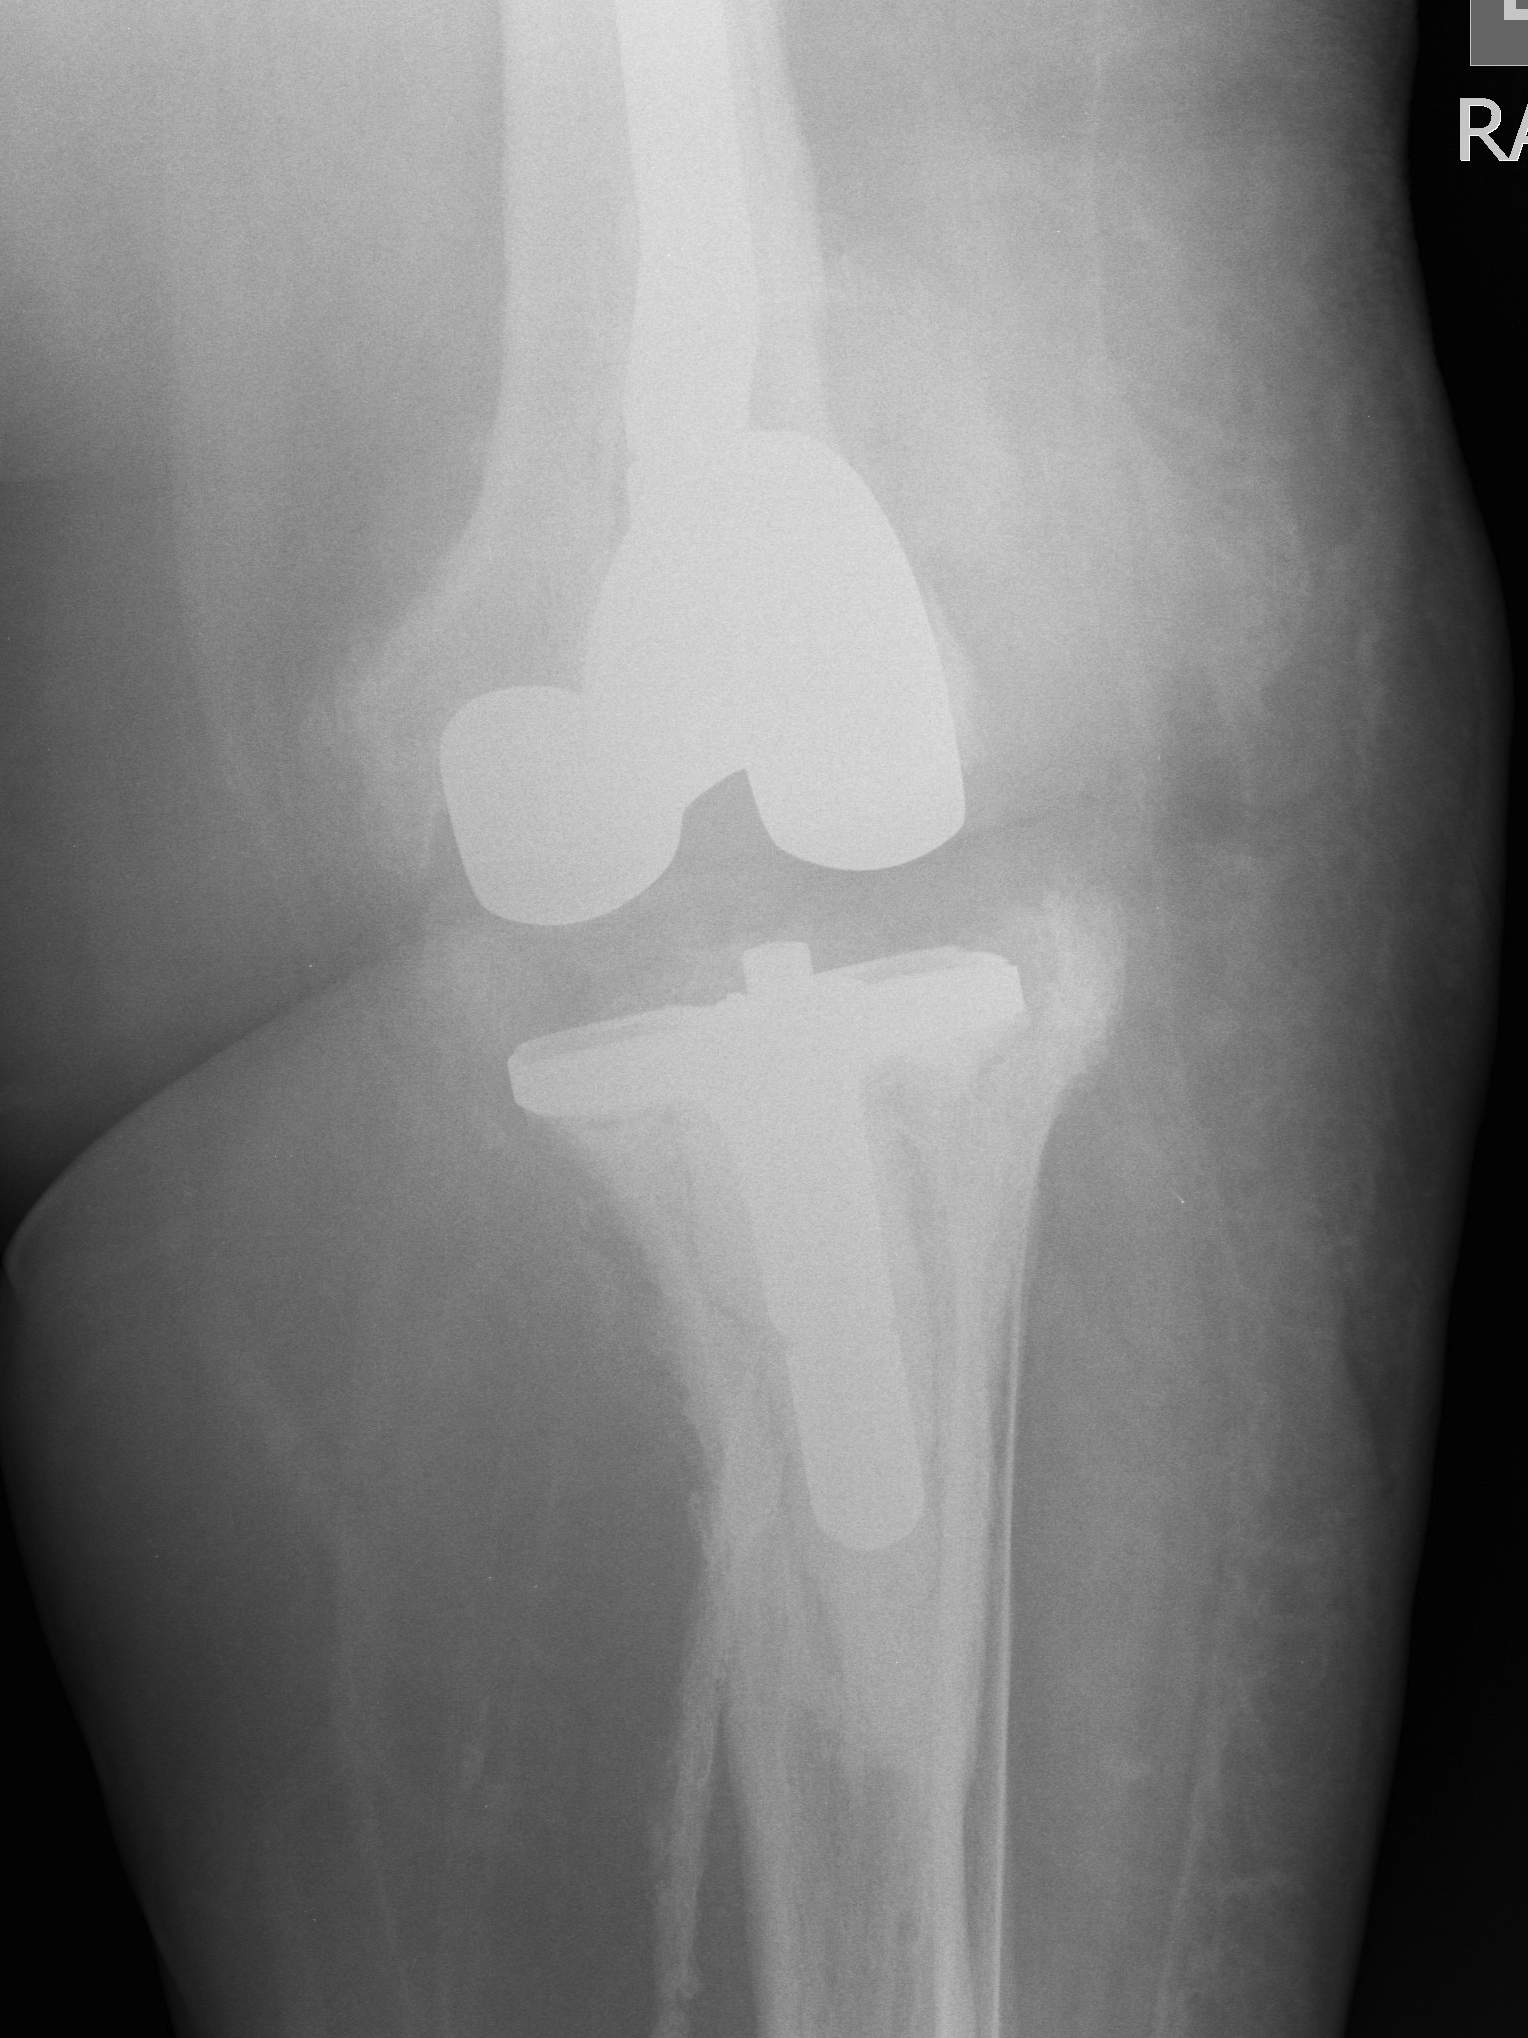

2. Two Stage Revision

Indication

- chronic infection

- Loose prosthesis

- failed early washout / debridement

2nd Stage

Insertion of stemmed revision prosthesis with augments

- constraint as required

- antibiotic cement